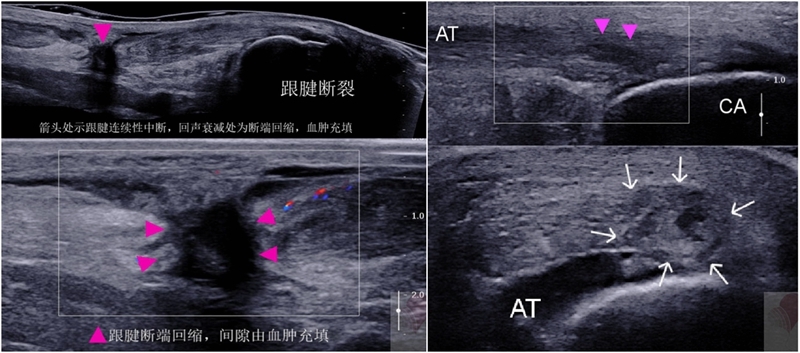

超声:跟腱断裂可以单纯通过临床检查做出诊断,但超声能够实现床旁快速确诊。尽管发表的资料有限,经验丰富的人员进行超声检查时,超声似乎是诊断跟腱撕裂、鉴别部分性和完全性跟腱撕裂的准确工具。

(1)完全跟腱断裂:肌腱纤维完全中断不连续,边缘呈锯齿状,由于组织水肿,肌腱断端收缩,超声学上表现肌腱回缩增粗,肌丝缺如,由于出血和渗出,裂隙中间为低回声区或无回声区。

(2)部分跟腱撕裂:跟腱纤维的部分连续性好,部分不连续,不连续的肌腱纤维之间及周围可见低回声区或无回声区。